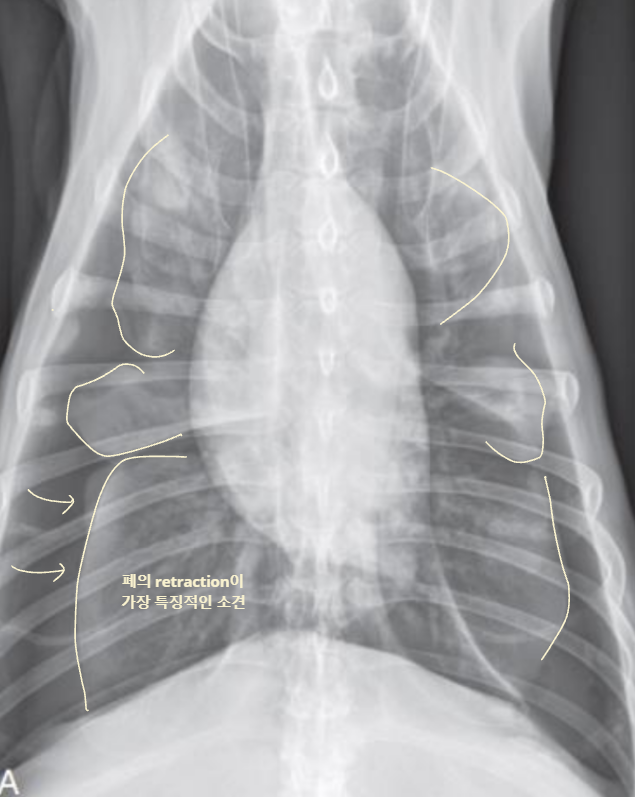

4. Pleural Space

| Pleural effusion (ํ์) | Pneumothorax (๊ธฐํ) | |

|---|---|---|

| ํ๊ฐ(pleural cavity)์ ๋ฌผ์ด ์ฐฌ ๊ฒ (ํ์ ์ฐจ๋ฉด โ ํ์์ข ) | ํ๊ฐ์ ๊ณต๊ธฐ๊ฐ ์ฐฌ ๊ฒ (ํ์ ์ฐจ๋ฉด โ ํ๊ธฐ์ข ) | |

| Radiographic signs interlobar fissure ๋๊ป๊ฒ ๊ด์ฐฐ๋๊ณ , ํ๋ฒฝ์ด ๋จ์ด์ ธ ๋๊ฐ ๊ฒ์ฒ๋ผ ๋ณด์ | Radiographic signs ์ฌ์ฅ์ด ๋ ์๊ณ , ํ๊ฐ ์ชผ๊ทธ๋ผ๋ฆ | |

| - Interlobar fissure widening - Lung retraction - Pleural wall thickening - Scallop sign - Cardiac effacement - Blunt angle | - Retraction of pleural surface - Collapsed lung (โ opacity ์ฆ๊ฐ) | |

![]() | ![]() | |

![]() ![]() | ![]() ![]() | |